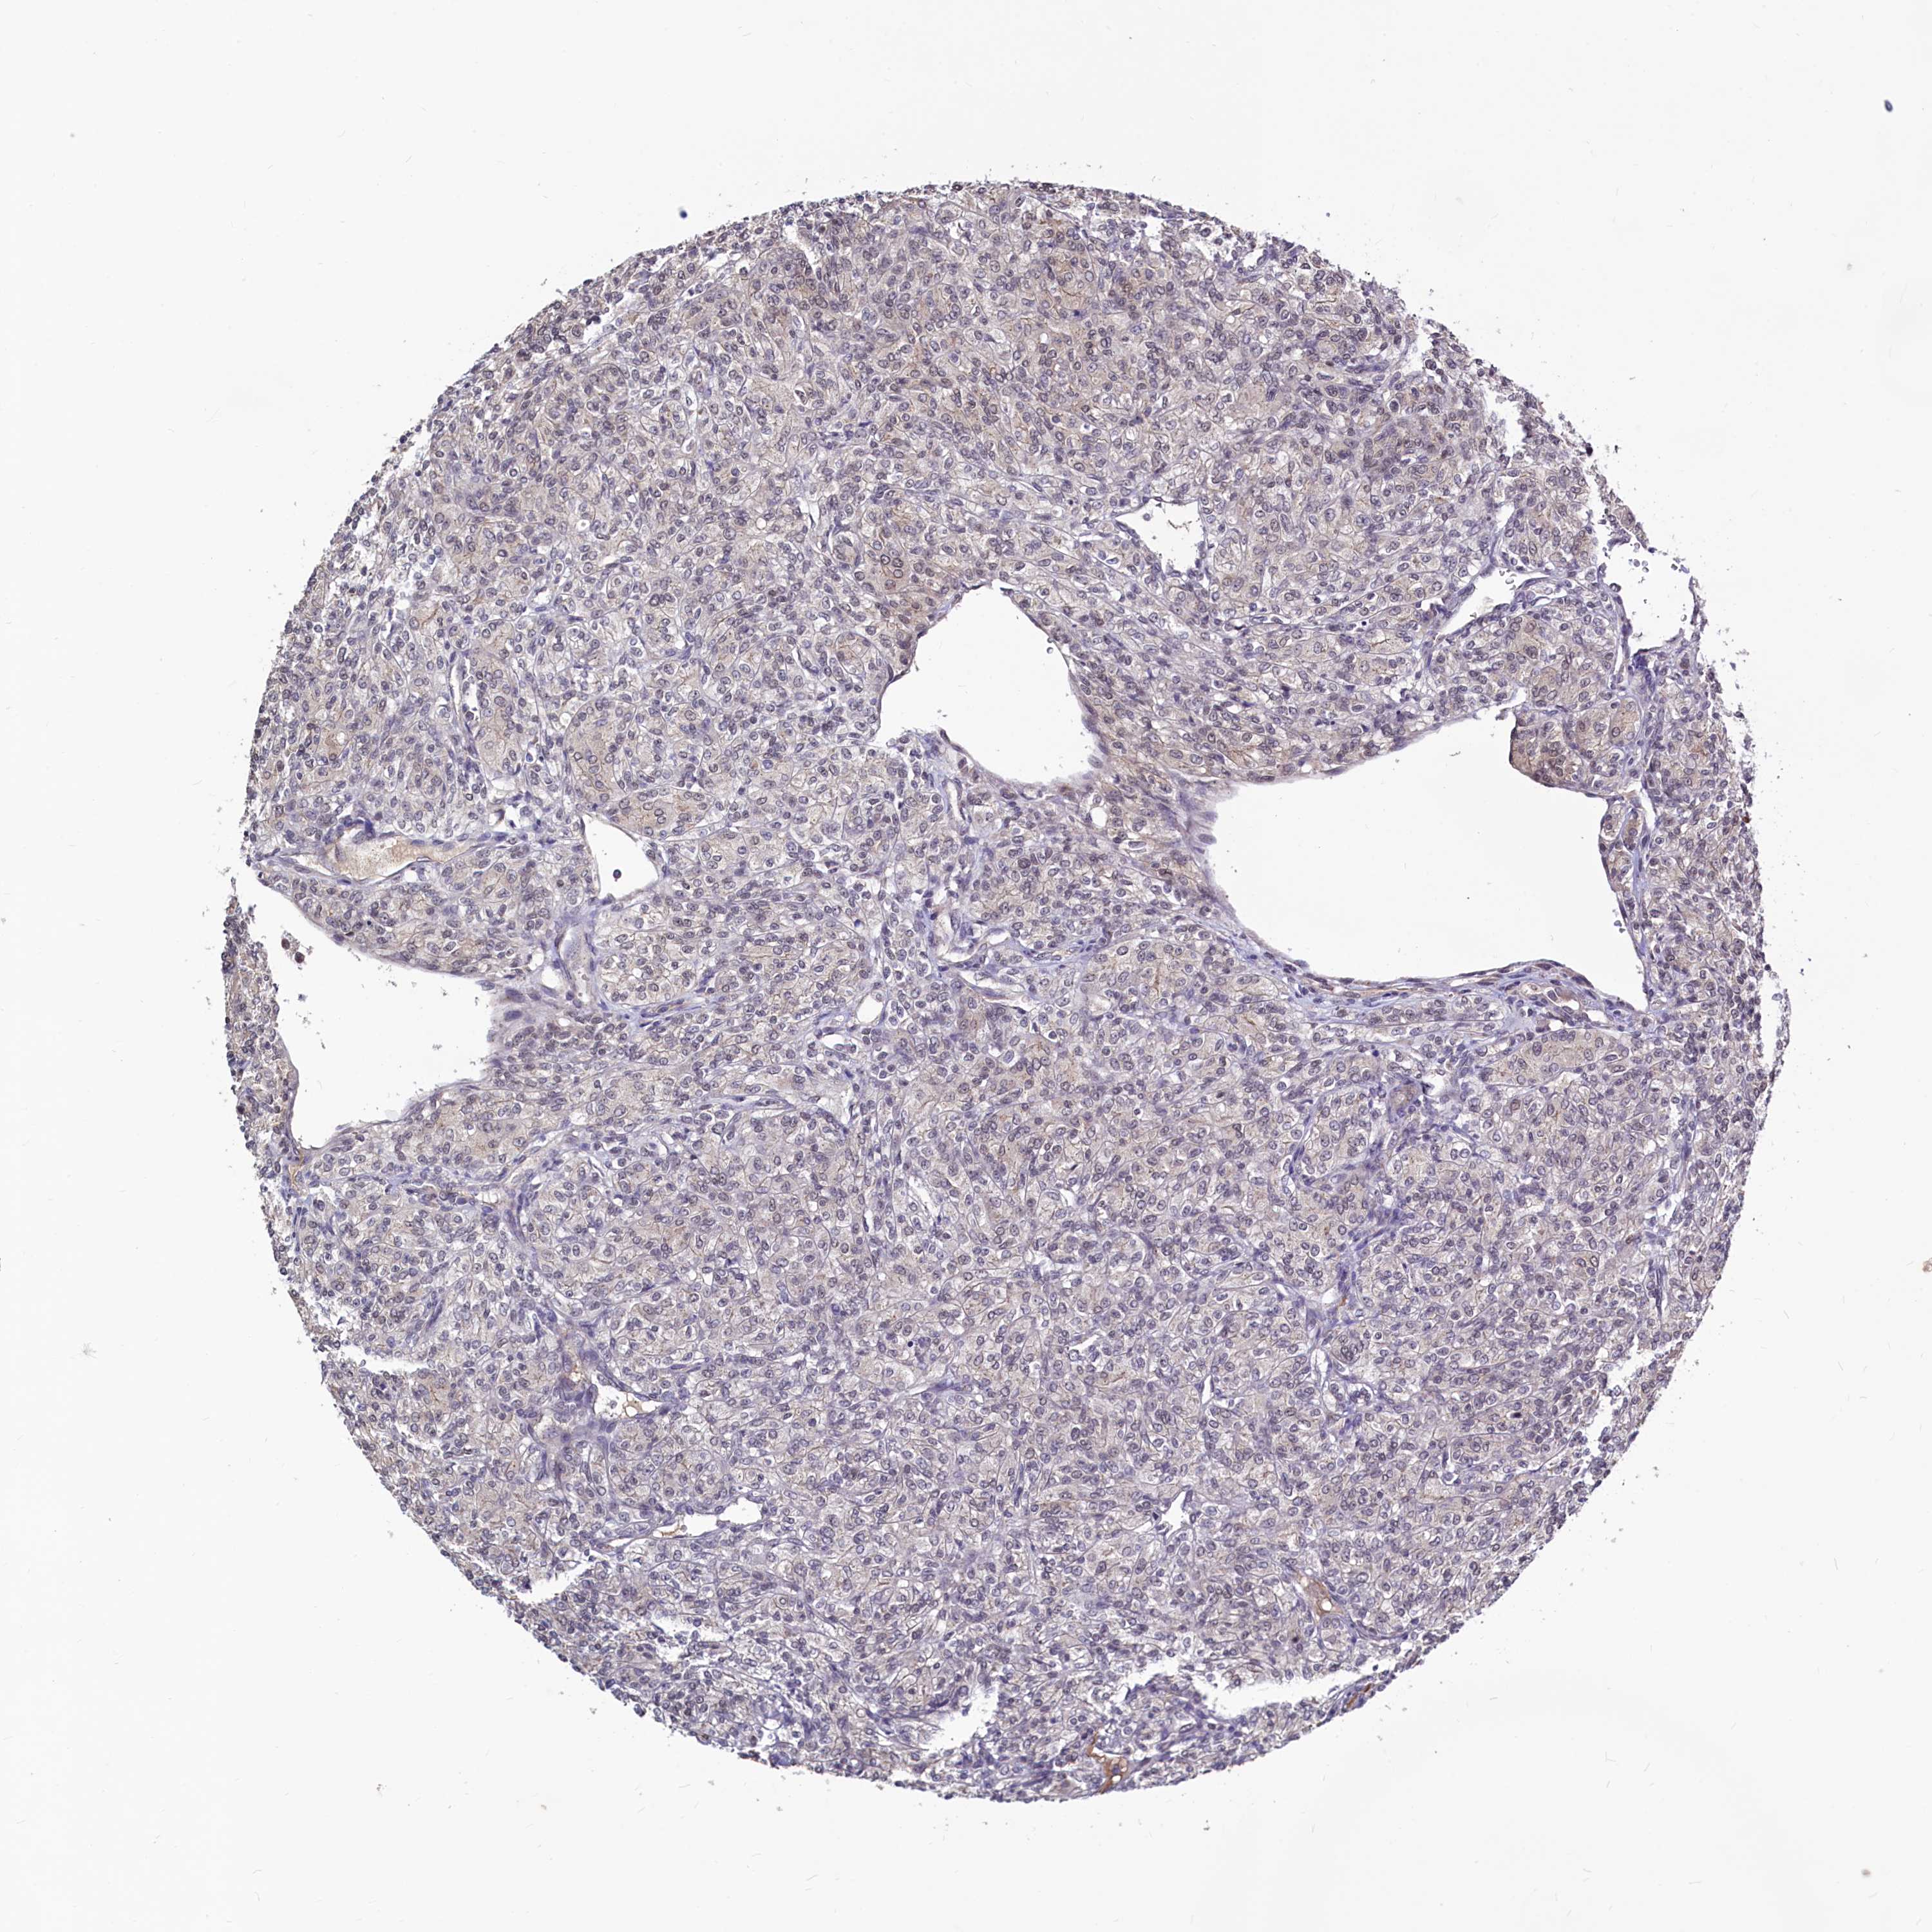

KIDNEY RENAL CLEAR CELL CARCINOMA (VALIDATION) - Interactive survival scatter ploti

The Survival Scatter plot shows the clinical status (i.e. dead or alive) for all individuals in the patient cohort, based on the same data that underlies the corresponding Kaplan-Meier plots. Patients that are alive at last time for follow-up are shown in blue and patients who have died during the study are shown in red.

The x-axis shows the expression levels (FPKM) of the investigated gene in the tumor tissue at the time of diagnosis. The y-axis shows the follow-up time after diagnosis (years). Both axes are complimented with kernel density curves demonstrating the data density over the axes. The top density plot shows the expression levels (FPKM) distribution among dead (red) and alive patients (blue). The right density plot shows the data density of the survived years of dead patients with high and low expression levels respectively, stratified using the cutoff indicated by the vertical dashed line through the Survival Scatter plot. This cutoff is automatically defined based on the FPKM cutoff that minimizes the p-score. The cutoff can be changed by dragging the vertical line or by entering a cutoff value in the square labeled "Current cut-off".

Under the Survival Scatter plot the p-score landscape (black curve; left axis) is shown together with dead median separation (red curve; right axis). Dead median separation is the difference in median mRNA expression between patients who have died with high and low expression, respectively. It is calculated as follows: median FPKM expression of dead patients with high expression - median FPKM expression of dead patients with low expression. This is intended to aid the user in visually exploring custom cutoffs and the associated p-scores and dead median separation.

Individual patient data is displayed and can be filtered by clicking on one or more of the category buttons on the top of the page. Categories describing expression level and patient information include: high, low, alive, dead, female, male and tumor stages. The scale of the x-axis can be toggled between linear and log-scale by clicking on the "x log" button. Mouse-over function shows TCGA ID, patient information and mRNA expression (FPKM) for each patient.

& Survival analysisi

Kaplan-Meier plots summarize results from analysis of correlation between mRNA expression level and patient survival. Patients were divided based on level of expression into one of the two groups "low" (under cut off) or "high" (over cut off). X-axis shows time for survival (years) and y-axis shows the probability of survival, where 1.0 corresponds to 100 percent.

SEC24C is not prognostic in Kidney Renal Clear Cell Carcinoma (validation)

Best expression cut offi

Based on the FPKM value of each gene, patients were classified into two groups and association between prognosis (survival) and gene expression (FPKM) was examined. The best expression cut-off refers the FPKM value that yields maximal difference with regard to survival between the two groups at the lowest log-rank P-value. Best expression cut-off was selected based on survival analysis .

When clicking on this number, the vertical dashed line indicating cut-off, the interactive survival plot, and the Kaplan-Meier curve will be adjusted to show results based on the best expression cut-off.

: 44.65

Median expressioni

Median expression refers to the median FPKM value calculated based on the gene expression (FPKM) data from all patients in this dataset. When clicking on this number, the vertical dashed line indicating cut-off, the interactive survival plot, and the Kaplan-Meier curve will be adjusted to show results based on the median expression.

: N/A

Median follow up timei

Median follow up time refers to the median time (years) after diagnosis with this type of cancer, based on clinical data from all patients in this dataset.

P scorei

Log-rank P value for Kaplan-Meier plot showing results from analysis of correlation between mRNA expression level and patient survival.

N/A

5-year survival highi

5-year survival for patients with higher expression than the expression cutoff.

For melanoma and glioma, 3-year survival is shown.

5-year survival lowi

5-year survival for patients with lower expression than the expression cutoff.

TCGA RNA samplesi

RNA-seq data is reported as average FPKM (number Fragments Per Kilobase of exon per Million reads), generated by the The Cancer Genome Atlas (TCGA) .

Normal distribution across the dataset is visualized with box plots, shown as median and 25th and 75th percentiles. Points are displayed as outliers if they are above or below 1.5 times the interquartile range. FPKM values of the individual samples are presented next to the box plot.

Average pTPM 42.4

Number of samples 100